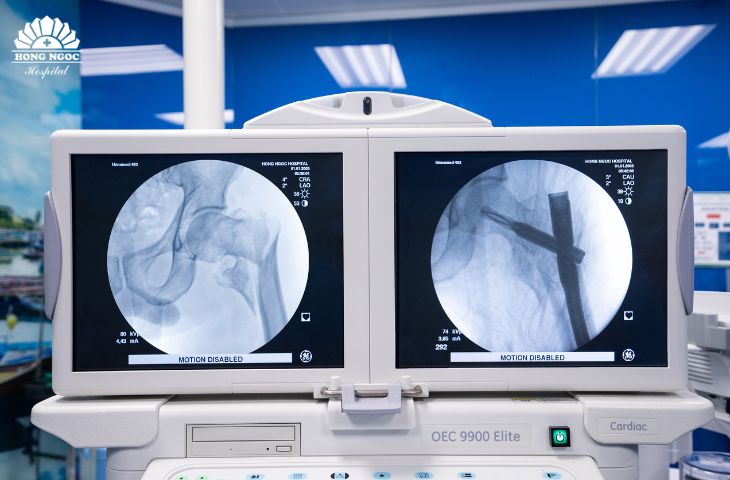

Căn cứ vào tình trạng sức khỏe của bệnh nhân, cùng kết quả hội chẩn liên khoa, TS.BS Lê Quang Huy (Khoa Ngoại Chấn Thương Chỉnh Hình - BVĐK Hồng Ngọc) quyết định nắn kín đưa các mảnh gãy về đúng vị trí và kết hợp xương bằng đinh nội tuỷ chống xoay, dưới định vị C-arm & bàn mổ chỉnh hình.

width= Tiến hành phẫu thuật kết hợp xương dưới C-arm

width= Liên mấu chuyển xương đùi - Trước và sau phẫu thuật